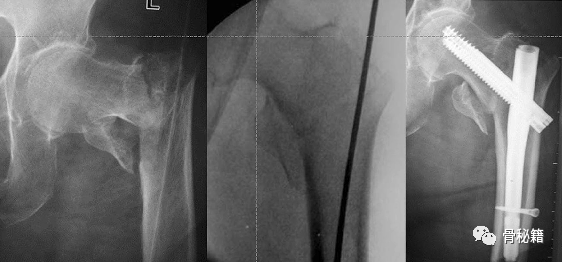

过于偏外的进针点导致髋内翻

进行调整后重新进钉